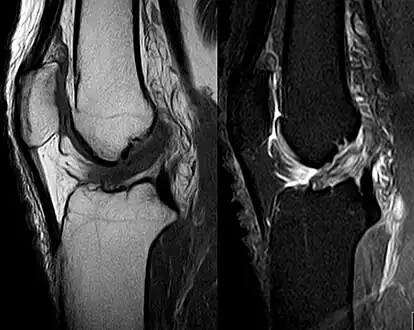

Though clinical examination in experienced hands can be accurate, the diagnosis is usually confirmed by magnetic resonance imaging, which provides images of the soft tissues like ligaments and cartilage around the knee.[1] It may also permit visualization of other structures which may have been coincidentally involved, such as the menisci or collateral ligaments.[29] An x-ray may be performed in addition to evaluate whether one of the bones in the knee joint was broken during the injury.[9]

MRI is perhaps the most used technique for diagnosing the state of the ACL, but it is not always the most reliable technique as the ACL can be obscured by blood that fills the joint after an injury.[30]

Anterior cruciate ligament tear seen on MRI. T1 left, right PDW.